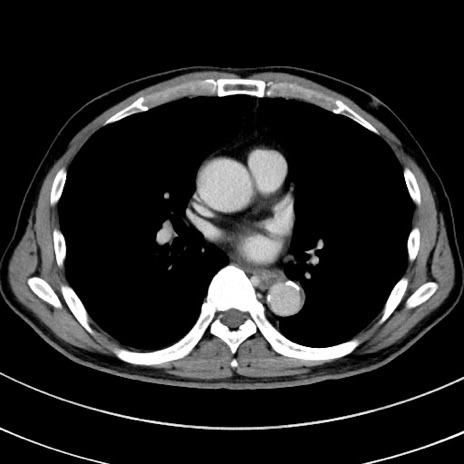

症例8(横断像)

【症例】 60歳代男性

【主訴】 黒色吐物

【現病歴】 4日前から嘔気自覚、2日前の朝食後にも嘔気あり、自分で手で嘔吐反射起こし嘔吐したところ血が混ざっていたため受診。

【既往歴】 5年前汎発性腹膜炎を伴う急性虫垂炎で手術、高血圧、前立腺肥大症、高脂血症

【身体所見】 腹部正中に手術癩痕あり 腹部平坦・軟圧痛なし膨満感あり

【データ】WBC 8400、CRP 4.54